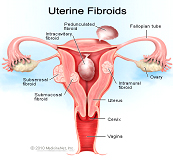

Infertility

Menstrual Irregularities